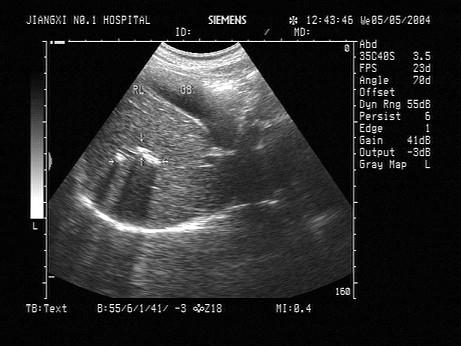

问题 男,42岁,体检,无明显不适。超声示肝内外胆管无明显扩张,肝右叶可见强回声条状回声,如图箭头所示异常光团,最可能的是?(?)

选项 A.管壁钙化 B.肝内胆管结石 C.胆道蛔虫 D.胆道气体 E.胆管癌

答案 A